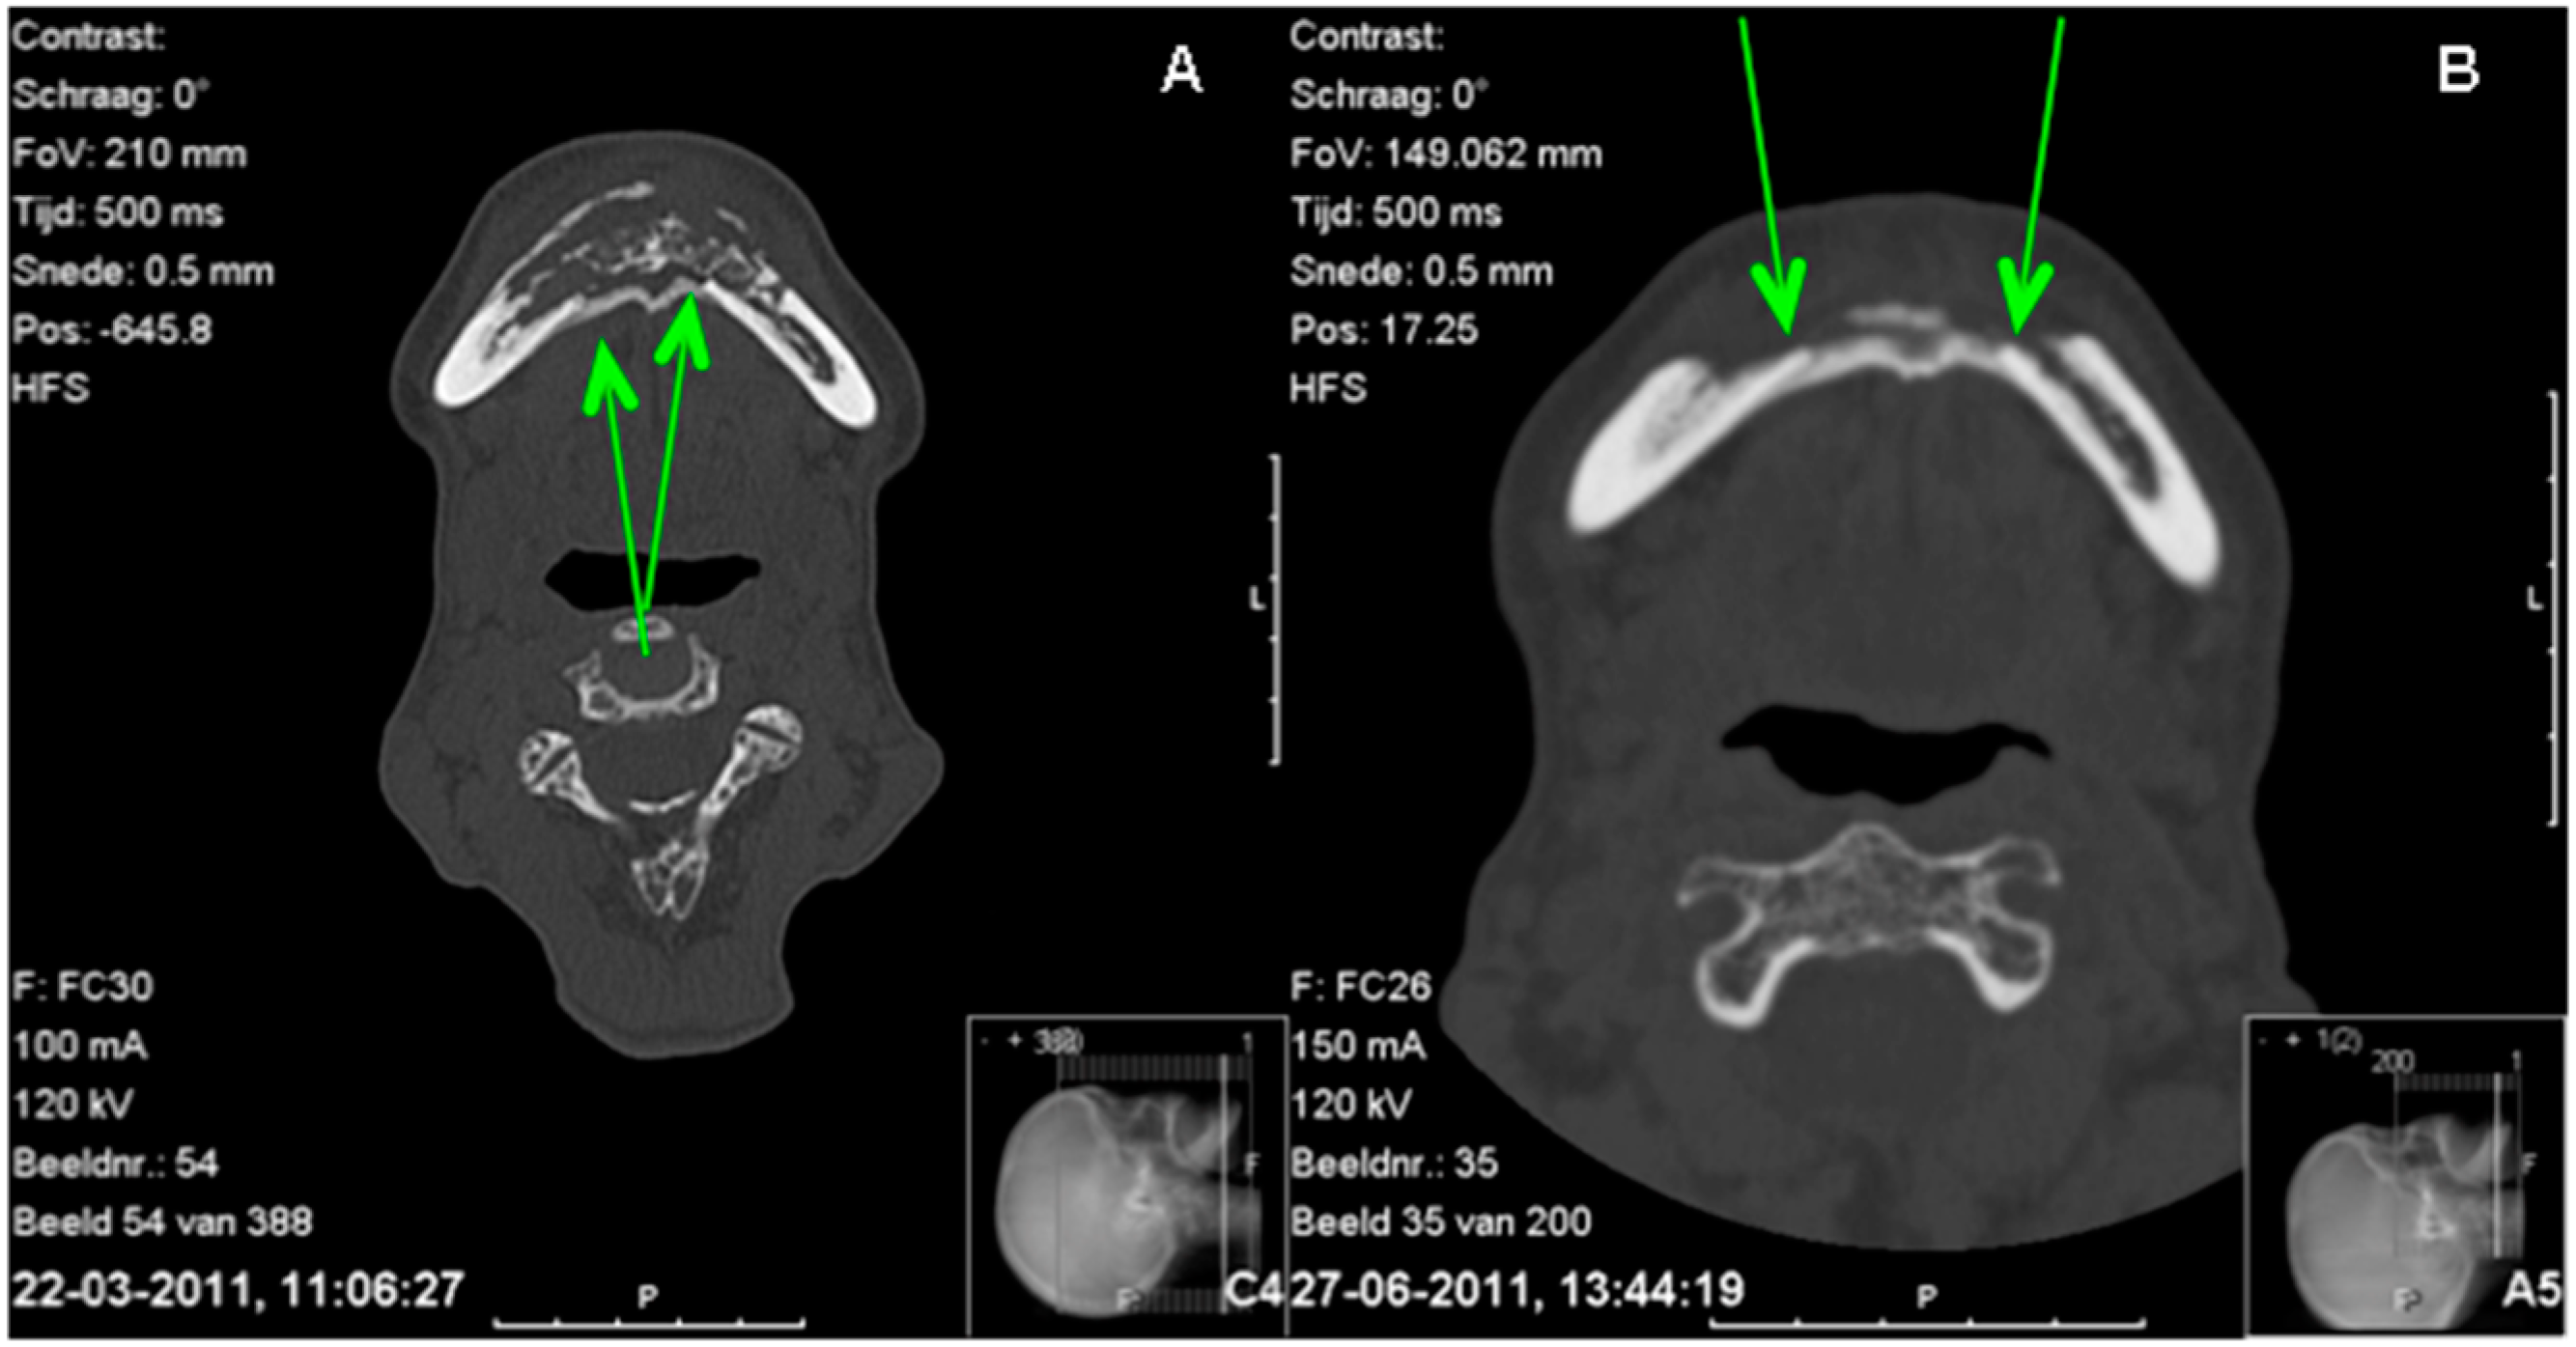

Figure 3.

Comparison CT scans before (A) and three months after surgery (B). A = lingual subperiosteal bone can be seen and seems to connect both parts of the mandible; B = the difference between the cortex of the mandible and the subperiosteal bone is decreasing.

The panoramic radiograph showed osteolysis of the ventral part of the mandible (Figure 2). The CT scan (Figure 3A) showed massive osteolysis and sequestration of the ventral part of the mandible from region 34 to 45, matching osteomyelitis and BRONJ. The continuity of the mandible seemed intact just because of subperiostal bone formation (Figure 3A).

The pre- and post-operative CT scan confirmed this finding: that the continuity of the original lingual cortex of the region from 34 to 45 was gone and replaced by subperiosteal bone (Figure 3B).

The CT scan also showed that the subperiostal bone developed a cortex-like structure (Figure 3B). The distinction between the former cortex of the mandible and the cortex of the neo-mandible was visible on the CT scan (Figure 3B). Where the first CT scan made at presentation clearly shows a distinction between the subperiosteal bone and the lingual cortex, the second CT scan made several weeks after presentation appears to have no such clear distinction anymore. It seems as if a new cortex has been formed.